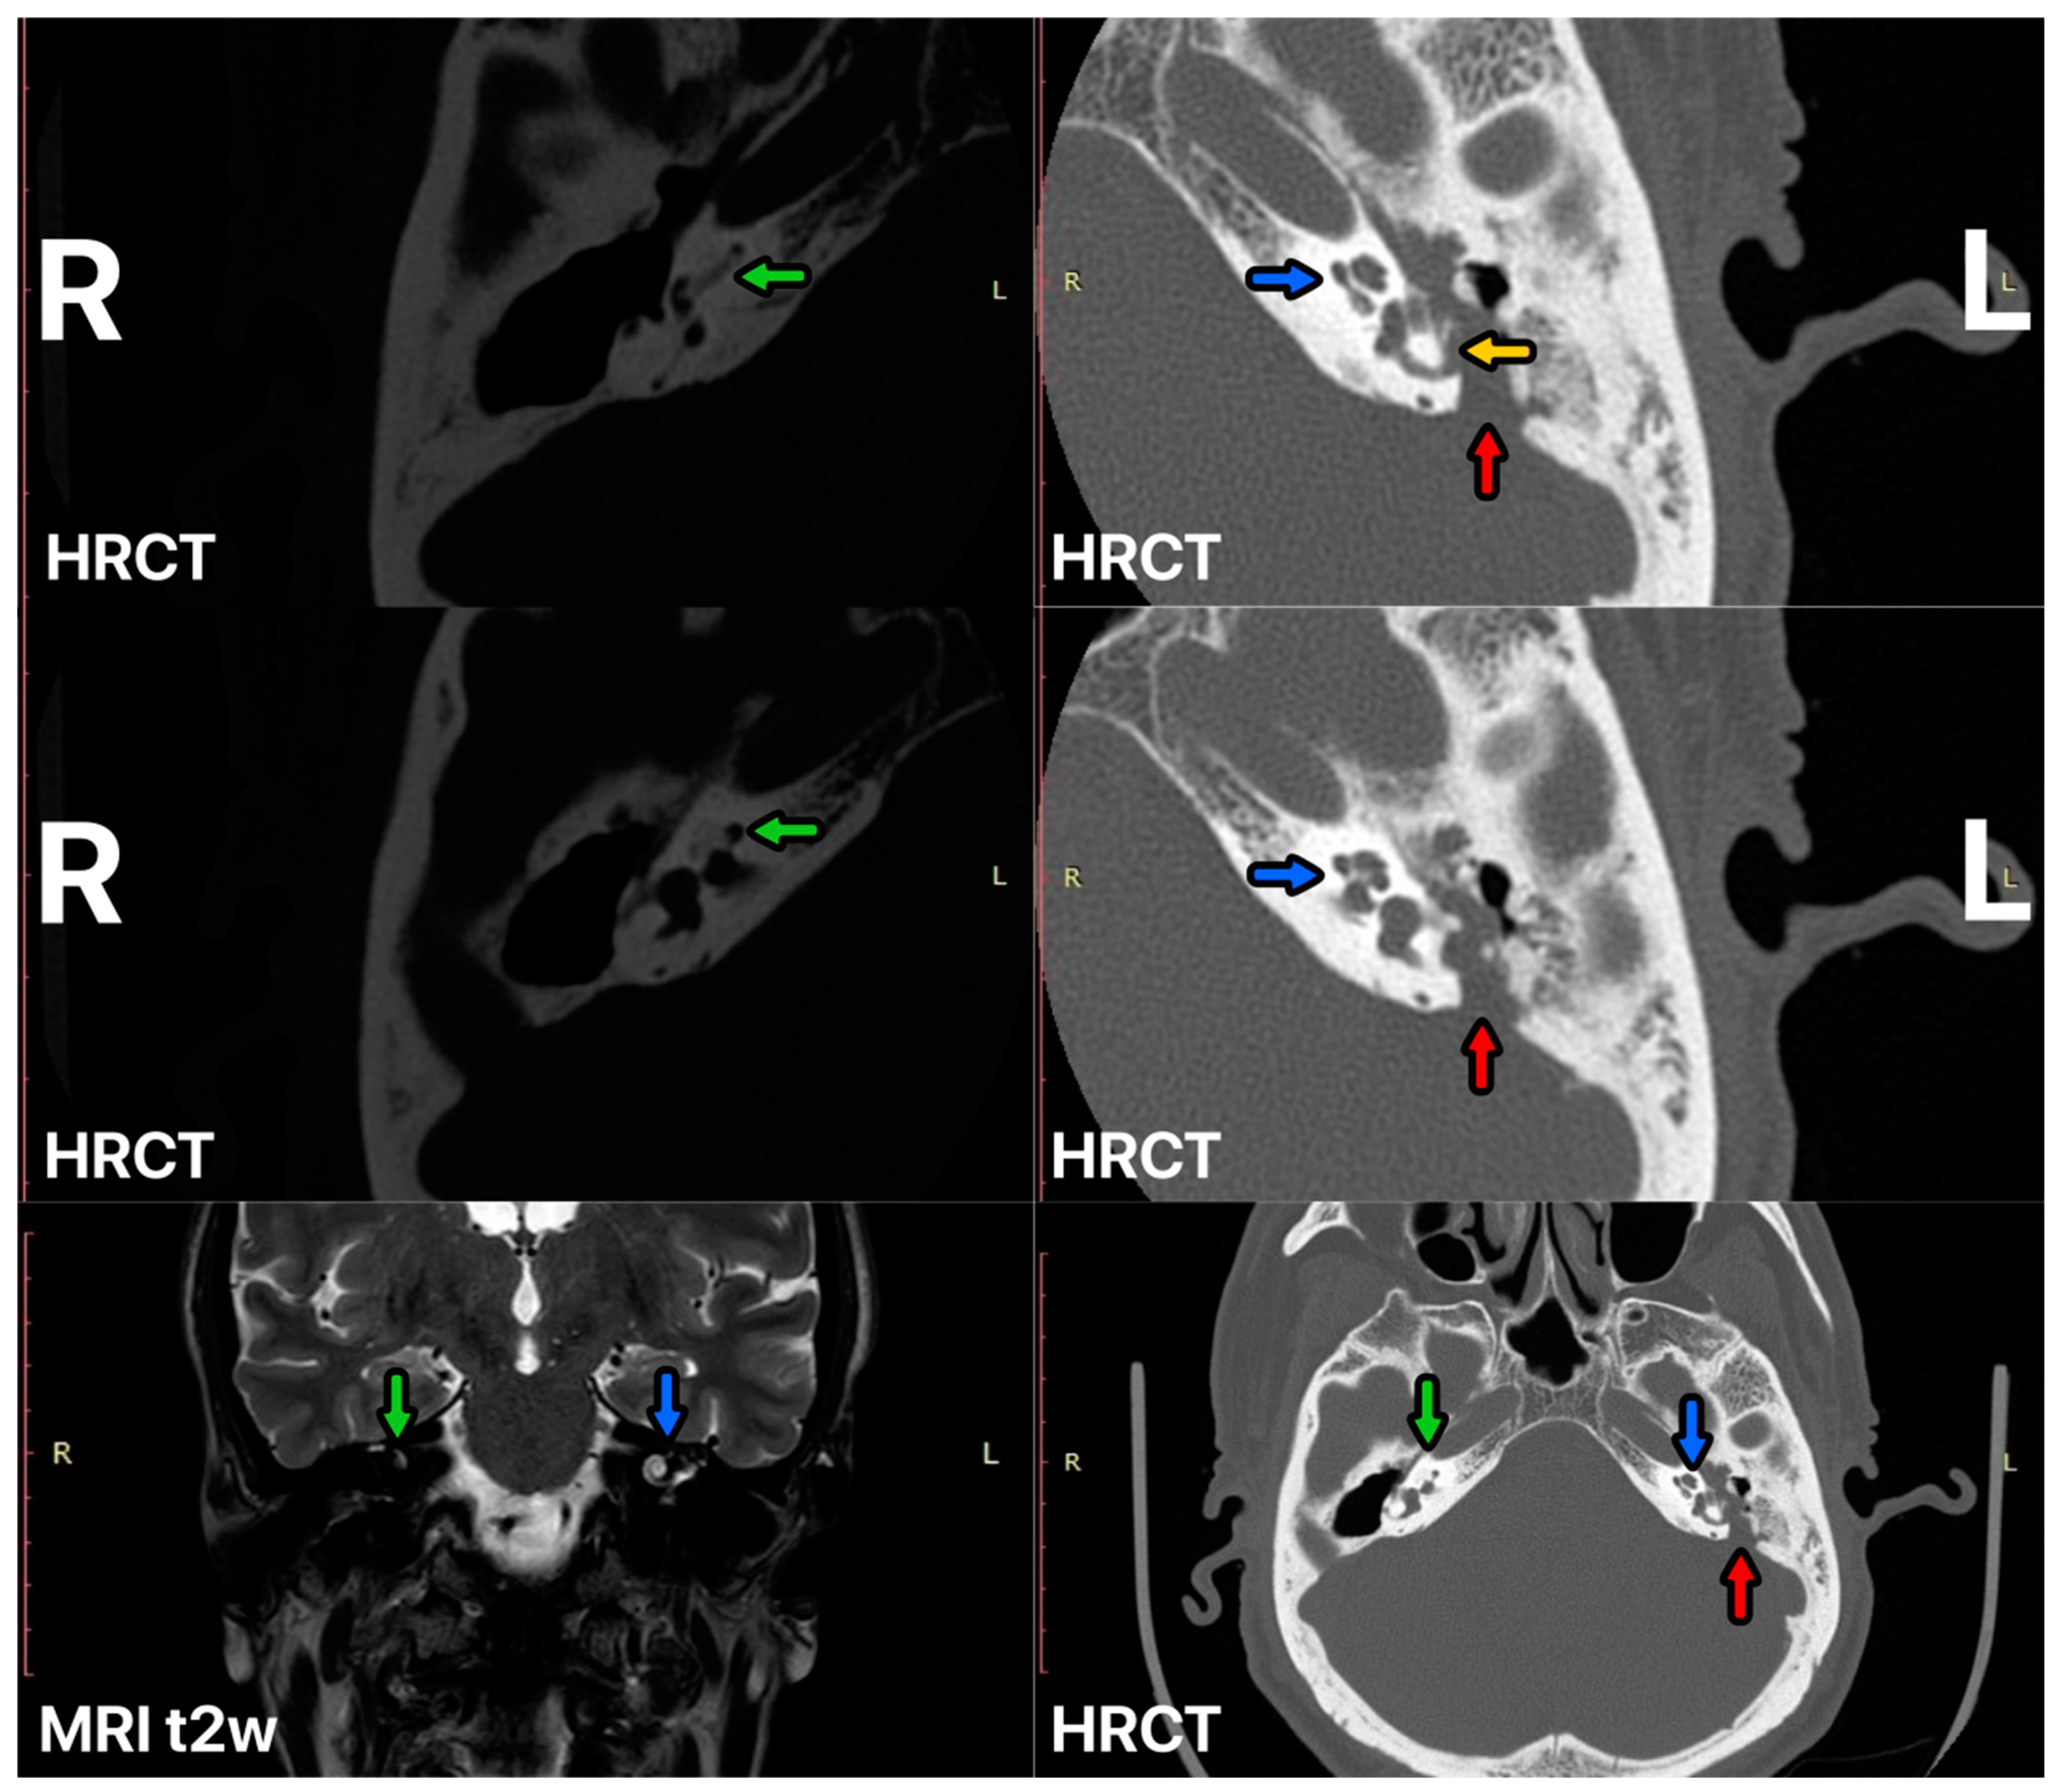

Figure 2.

HRCT and MRI of the ear before SP surgery. Right cochlear ossification—green arrow, left cochlear—blue arrow, posterior fossa destruction by cholesteatoma—red arrow, lateral semicircular canal destruction—yellow arrow.